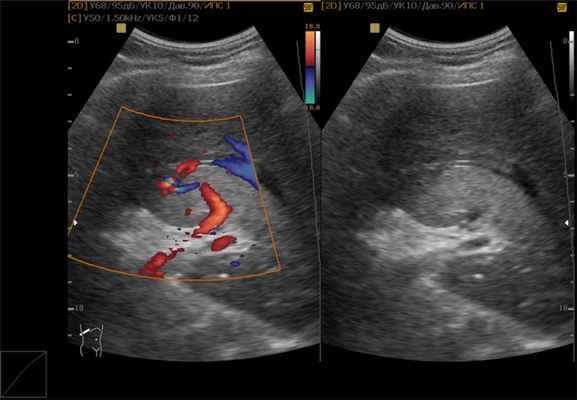

- контрастно-улучшенный ультразвук – высокочастотные звуковые волны проходят через ткани тела, а эхо-сигналы записываются и преобразуются в видео или фотографии;

- и печени (может показать опухоль круглой формы с четкими границами); (помимо очертаний образования покажет и его содержимое); (послойно продемонстрирует границы и содержимое опухоли).

- Ультразвуковое исследование. Метод визуализации органов и анатомических структур. В его основе лежит использование высокочастотных звуковых волн, которые отражаются от органов, с формированием изображения.